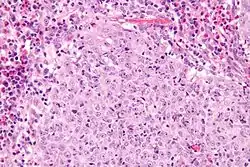

| Micrograph of a glassy cell carcinoma of the cervix. H&E stain. | |

Under the microscope, glassy cell carcinoma tumours are composed of cells with a glass-like cytoplasm, typically associated with an inflammatory infiltrate abundant in eosinophils and very mitotically active. PAS staining highlights the plasma membrane.[2]